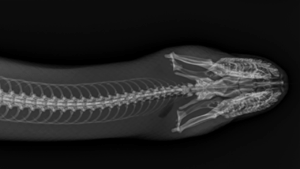

Anacondas

Capturing a clear radiograph of a snake takes patience and precision. Because even slight movement can blur the image, keeping them steady is essential.

To obtain good images of these naturally wiggly patients, we use light sedation to help them relax throughout the process. We may also use a snake tube, a clear device that allows the anaconda to rest safely inside while staying straight and still.

Much like with our seals and sea lions, the team takes a series of radiographs from head to tail, ensuring every inch of the lengthy patient is examined and recorded.